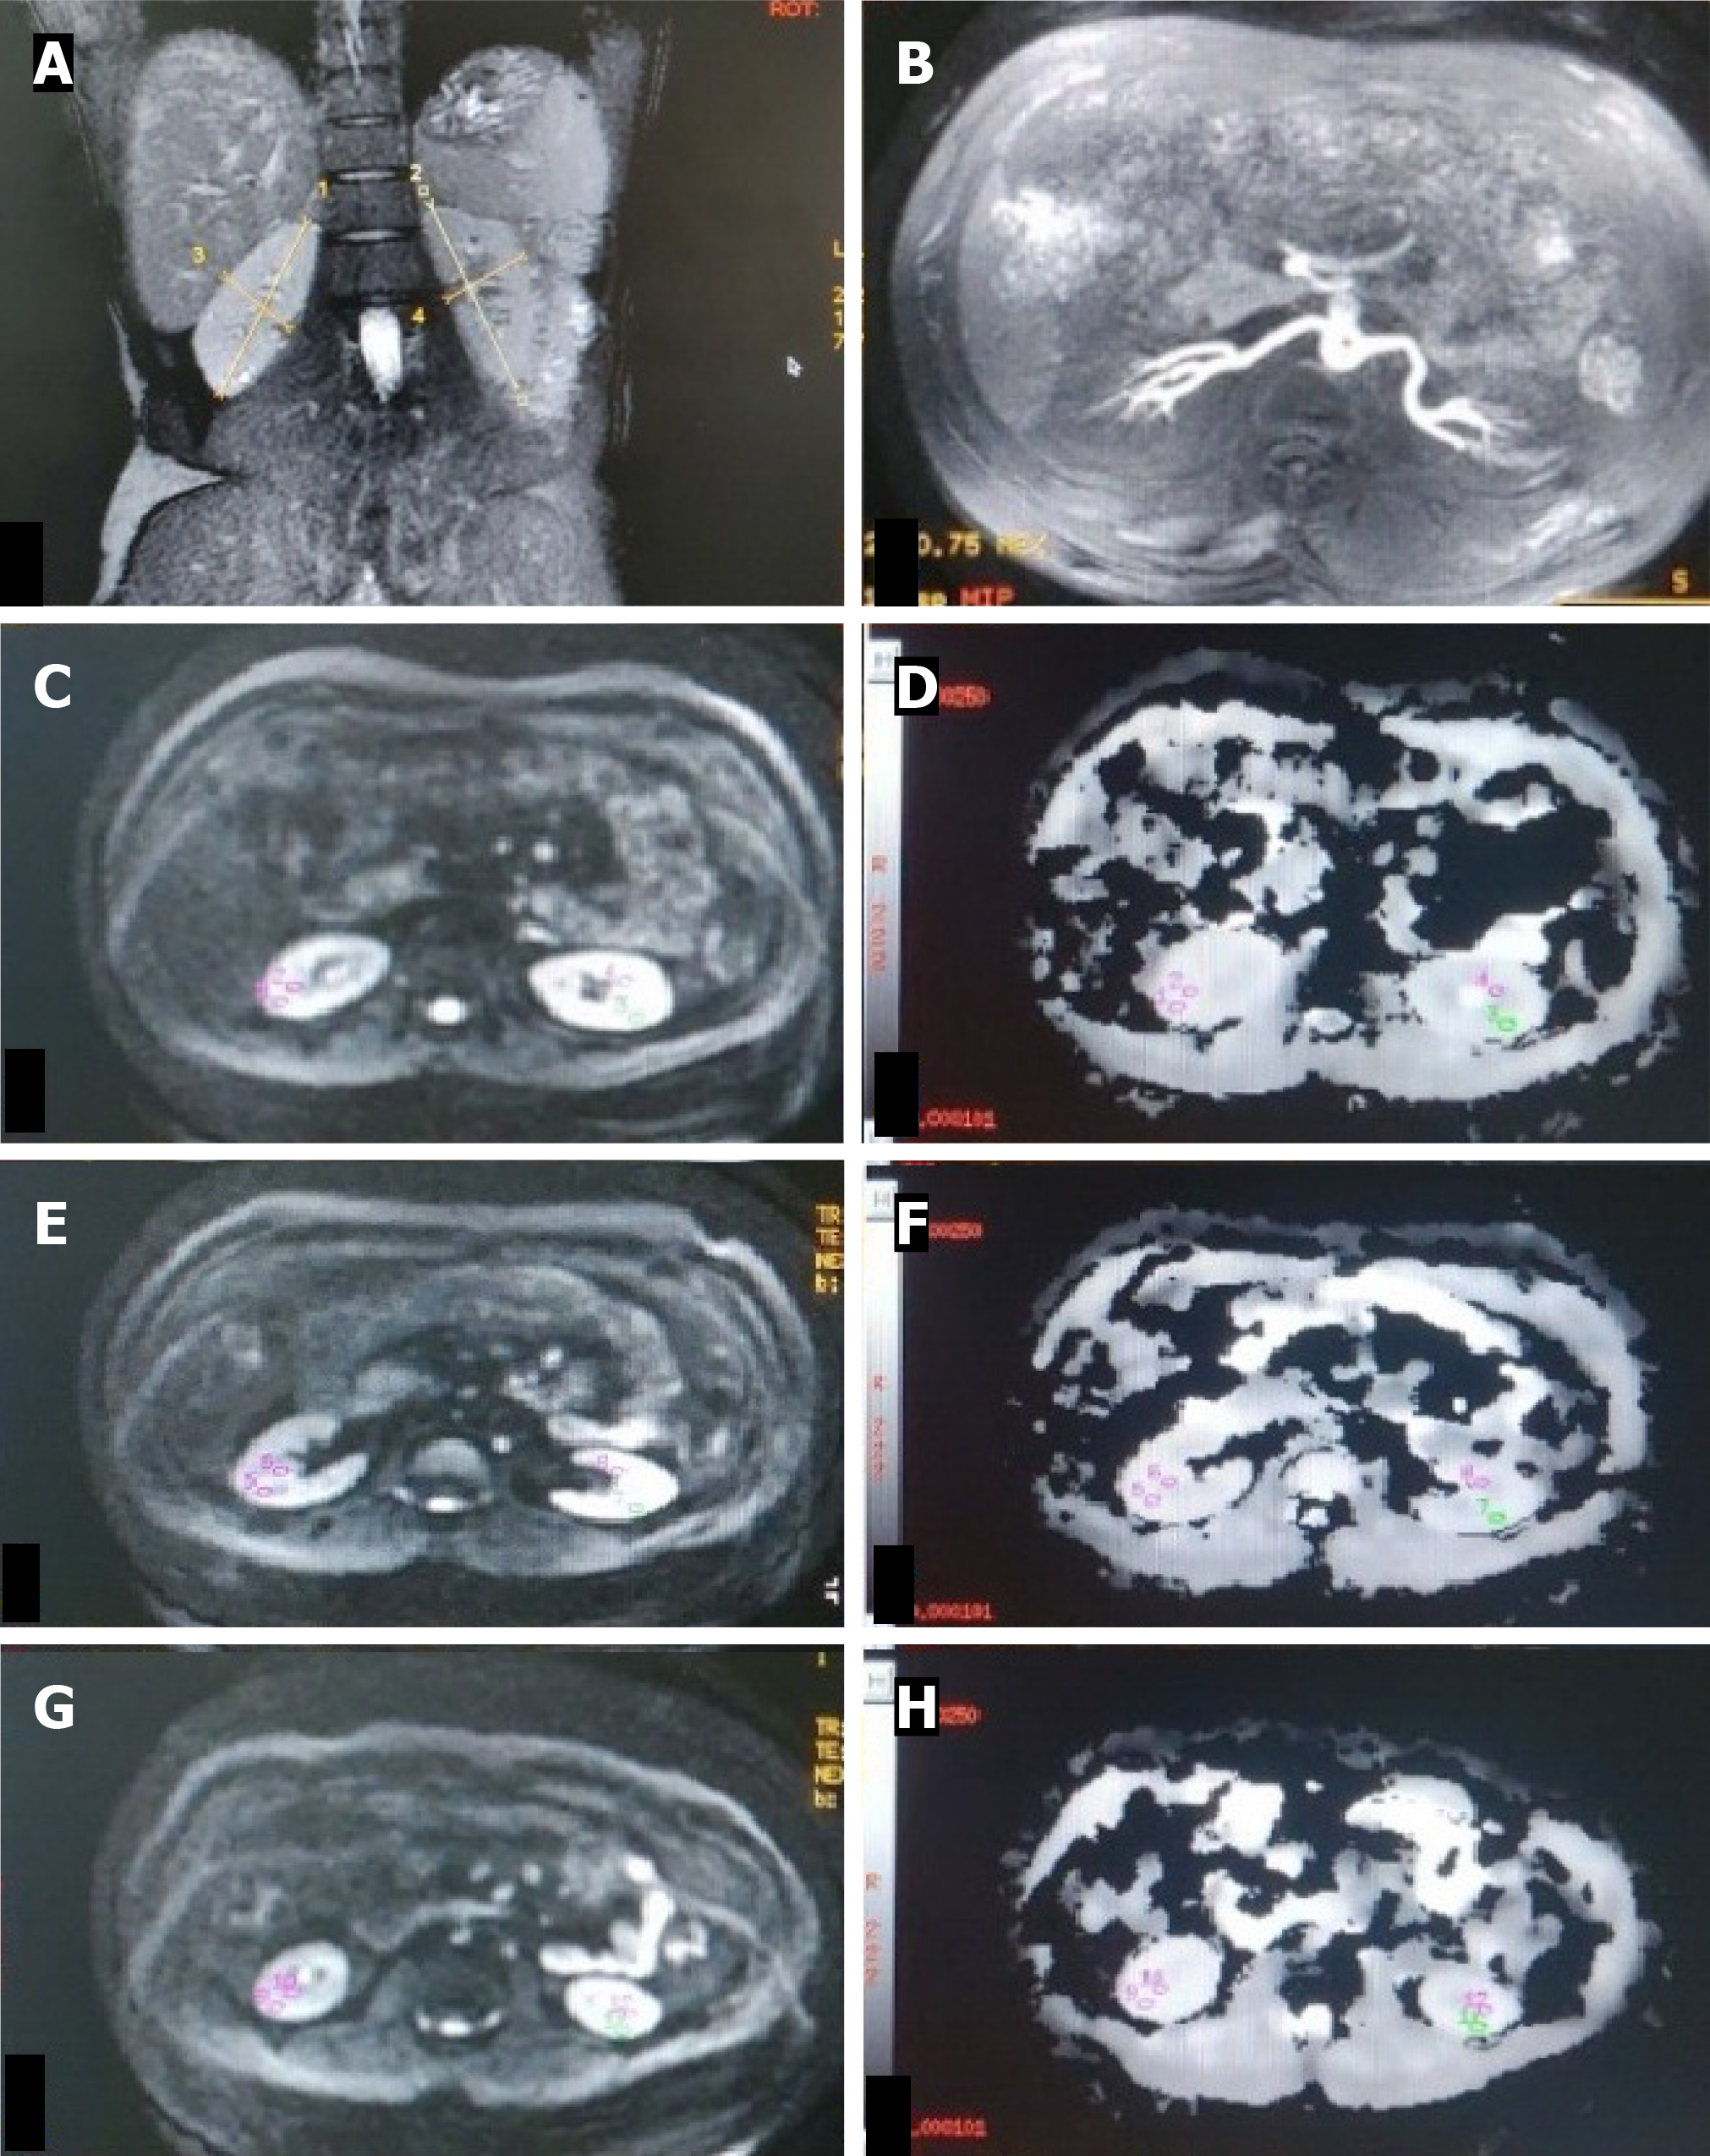

Figure 4 Hypertensive patient.

A: T2W magnetic resonance (MR) image (coronal plane) showing bilateral normal-sized kidneys (RK 8.9 cm, LK 8.9 cm); B: Non-contrast MR angiography (INHANCE) depicting bilateral normal renal arteries in the axial plane; C-H: Diffusion-weighted MR image (C, E, G) in the axial plane with corresponding apparent diffusion coefficient (ADC) map (D, F, H) of bilateral kidneys showing manually drawn region-of-interest (ROI) placed in the upper (C, D), middle (E, F) and lower (G, H) pole regions of bilateral kidneys. The ROI is placed in the cortex and medulla on both sides. Mean cortical ADC and medullary ADC values of the right kidney were 191 × 10-3 mm2/s and 1.86 × 10-3 mm2/s. Mean cortical ADC and medullary ADC values of the left kidney were 189 × 10-3 mm2/s and 1.82 × 10-3 mm2/s, respectively.